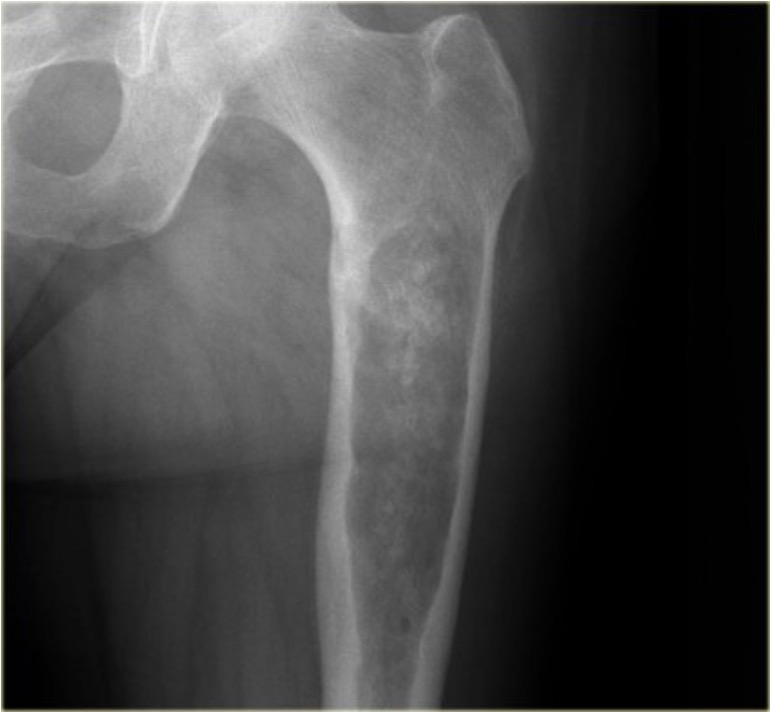

X-ray

Lytic lesion with punctate or spotty calcification

Worrisome features

- growth over time

- large > 5cm

- endosteal scalloping is hallmark of chondrosarcoma

Large calcified lesion with endosteal scalloping